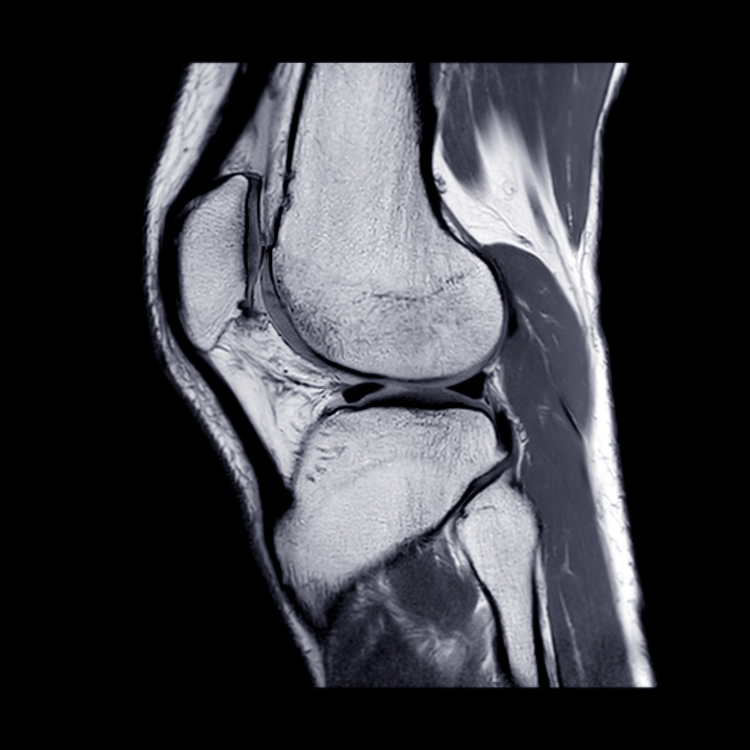

Rehabilitation following an ACL injury or reconstruction is a critical component of recovery, with a well-structured exercise plan being essential for restoring knee function, strength, and stability. Traditionally, much attention has been given to the type and timing of exercises—specifically open kinetic chain (OKC) and closed kinetic chain (CKC) exercises. But what are these exercises and how are they used in rehab?